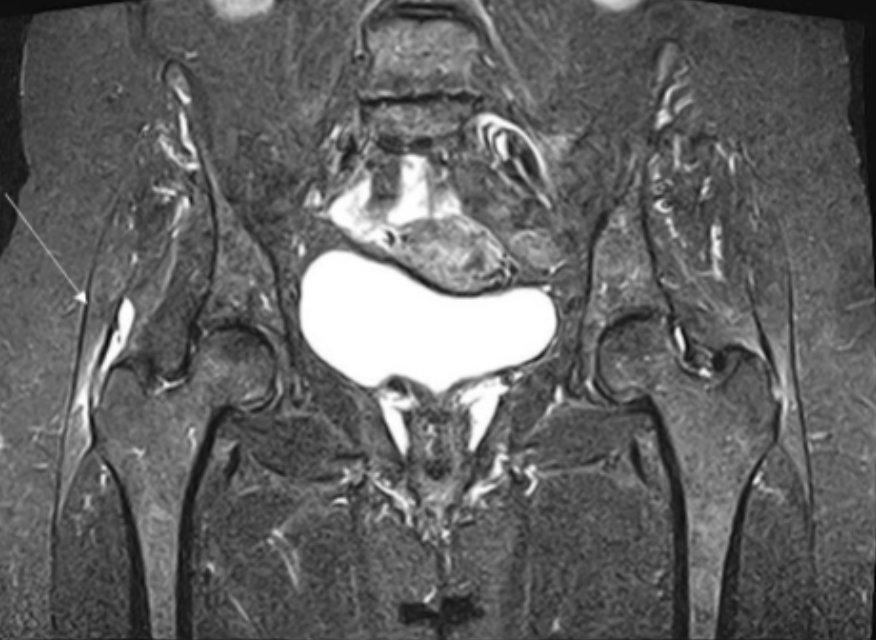

Describe the pathology indicated by the arrow (Cor T2 STIR pelvis).

Trochanteric bursitis